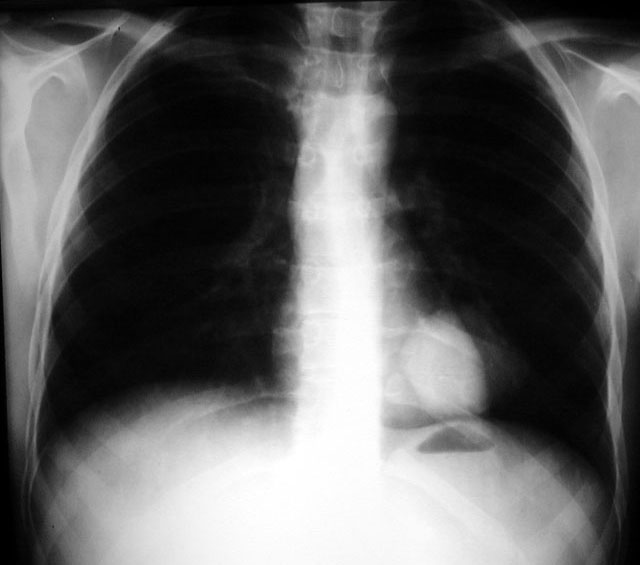

Malignant Melanoma

Metastatic to Lung

• Mass density LLL

• Inhomogenous cardiac density

• Retrocardiac

Lateral and IVP films below.

Calcified Adrenal Gland - Incidental finding